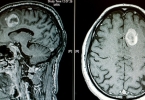

发现患者颞顶叶脑出血时,需要到医院进一步检查颞顶叶脑出血的原因。如果是中老年患者,伴有严重的高血压疾病,血压有时超过200毫米,可能是高血压脑出血。患者脑出血量超过30ml,意识状态不断下降,应尽快进行相关 ...